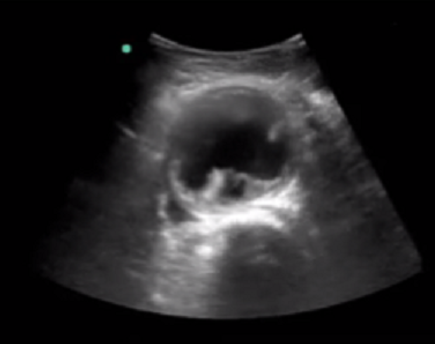

RUSH 腹主动脉瘤 (AAA) 图像